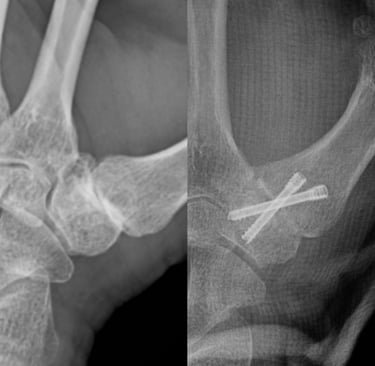

Estabilidad definitiva para casos avanzados

La artrodesis trapeciometacarpiana por artroscopia permite tratar la rizartrosis avanzada mediante la fusión controlada de la articulación, preservando la biomecánica del pulgar y reduciendo el dolor de forma definitiva. La asistencia artroscópica facilita una preparación precisa de las superficies articulares y una mínima agresión tisular, mientras que los tornillos canulados cruzados aportan una fijación sólida y fiable.

Rizartrosis avanzada o colapso severo con deformidad establecida (Eaton III–IV).

Pacientes jóvenes o muy activos, menos de 50 años, que priorizan fuerza y estabilidad sobre la movilidad.

Pacientes con trabajo manual intenso donde se requiere una solución definitiva y resistente.

Articulación con inestabilidad marcada o fracasos previos de otras técnicas.

Buena calidad ósea para garantizar la consolidación.